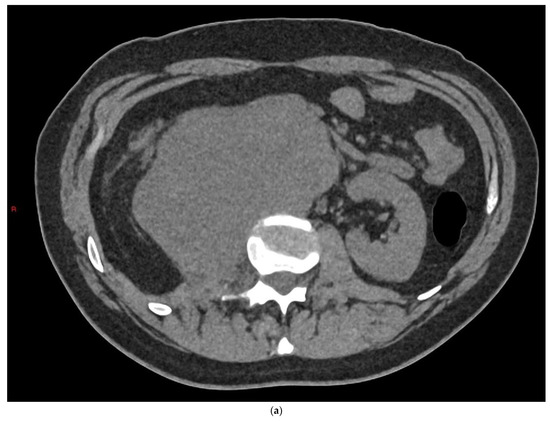

4.1. Seminomatous Germ Cell Tumour

| Seminomas | Homogenous and hypoechoic Well circumscribed Occasionally contain cystic components or calcifications |